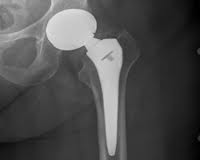

An U.K. woman has filed a product liability lawsuit against Wright Medical Technology, Inc. over problems with their Profemur hip replacement system, alleging that design defects caused the implant to suddenly break while she was walking. This is one of several Wright Profemur hip lawsuitsthat have been brought involving similar allegations.

Masters, who resides in Great Britain, received the implant in 2005 and alleges that last June, problems with the Wright Profemur hip replacement resulted in catastrophic failure of the medical device.

According to the complaint, the stem of the Wright hip implant probably had an oxygen rich metallic inclusion that occurred when the titanium alloy was in the liquid metal stage. The area around such inclusions tend to be brittle and cracked. In this case the crack was found at the point of maximum stress loading for the implant.

A number of other Wright hip replacement lawsuits have been filed on behalf of individuals who have experienced similar problems. Some complaints involve situations where the femoral neck of the Wright Profemur implant broke or fractured during normal use, resulting in severe pain and the need for revision surgery to replace the Wright Profemur hip system.